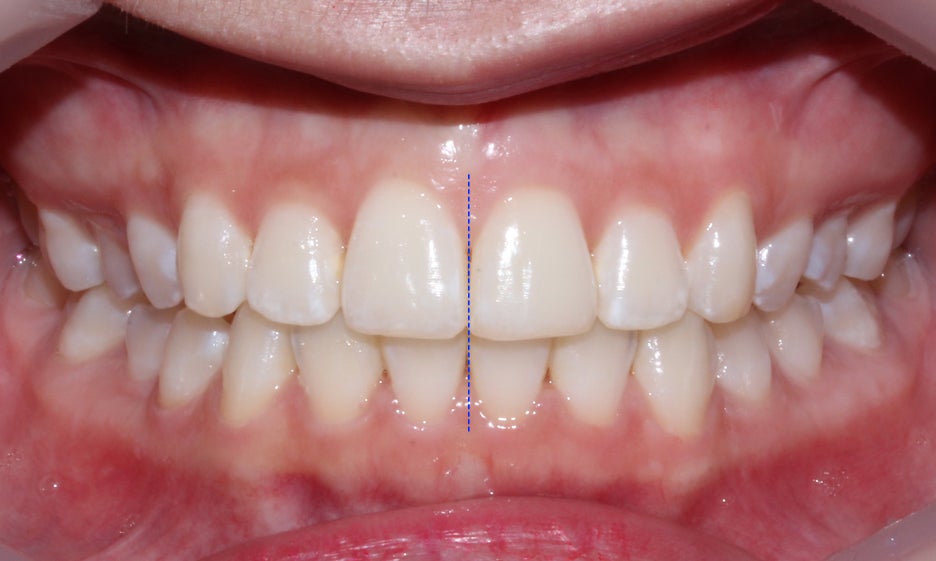

미소를 지었을 때 보이는 스마일라인의

치열을 보면 교정 후 포개져 있던 중절치가

바르게 배열되면서 가지런해진 모습으로

변위되었던 정중선도 일직선으로

바르게 맞춰진 것을 확인할 수 있습니다.

전치부의 측면 모습에서도 중절치가

돌출된 증상이 사라진 모습인데요,

교정 후 overjet과 overbite 수치도

정상적인 범위 내로 교정된 모습입니다.

교정 전 입술과 입매를 고려하여 과교정이

되지 않도록 하는 것인데요, 돌출증상을

교정하셨던 분들 중 일부가 과도하게

악궁의 길이를 줄이고 무리한 발치교정을

하셔서 '합죽이' 증상을 보이시는 분들도 있습니다.

따라서 이러한 과교정에 주의하며 정확한 정밀진단을 통해

발치와 치아이동을 계획하는 것이 중요합니다.